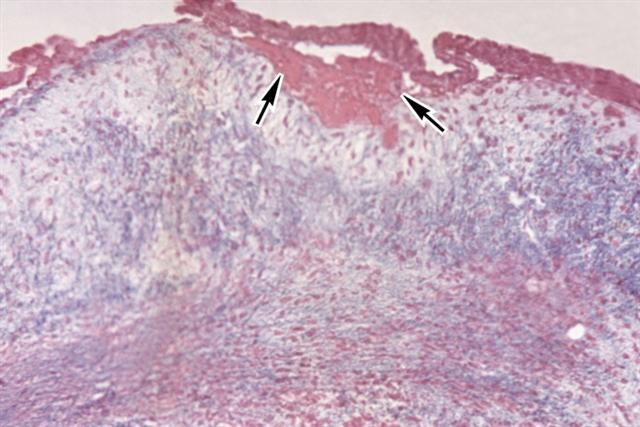

Рис. 1. Микропрепарат створки митрального клапана при эндокардите: отложение фибрина (указано стрелками) на отечной створке; окраска по Маллори; ´100.